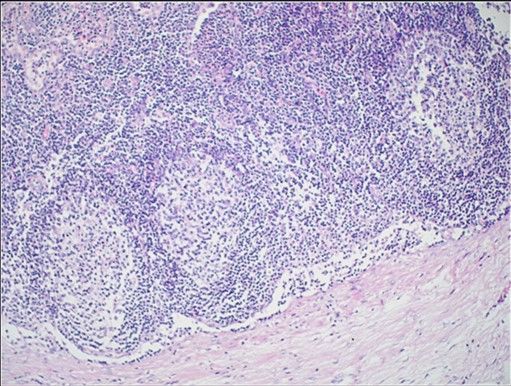

Question 7

Question

Label this image

Image:

dac35ad3-6c06-4446-90b7-a84c2cc12377 (image/jpeg)

Answer

Lymph Nodes